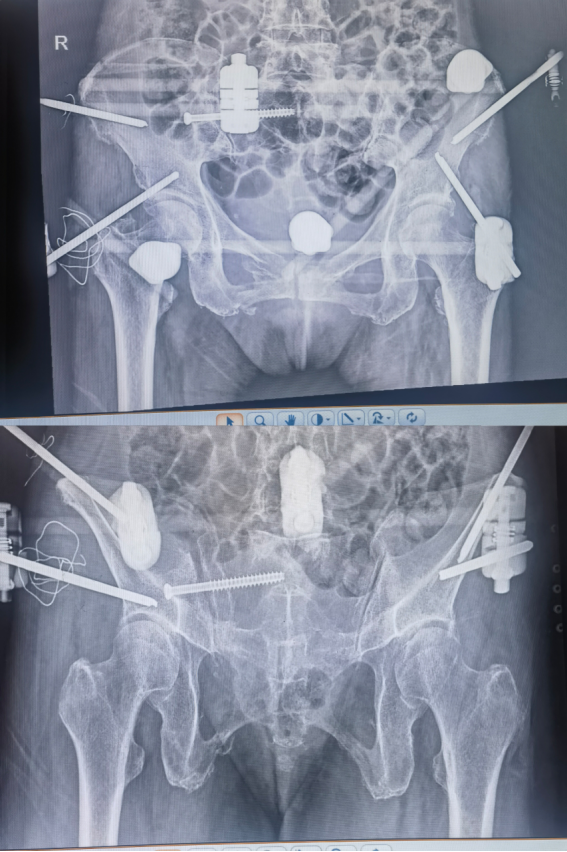

*术前:骨折部位移位明显,骨盆环倾斜

看到患者对自己高度信任,刘华水主任也非常感动,患者入院后立即完善术前相关检查,组织团队进行术前讨论,制定细致手术方案。入院48小时内即完成了术前准备,于10月31日一早进行手术。在手术室、麻醉科团队精心配合下,由刘华水主任主刀,在全身麻醉+静吸复合全麻下,行闭合复位微创螺钉修复破损严重骨盆骨折手术,手术过程仅用时30分钟,出血量不足10ml,术后立即可以活动,手术效果立竿见影,圆满达到预期效果。

*术后:骨盆骨折闭合复位满意,微创螺钉稳妥